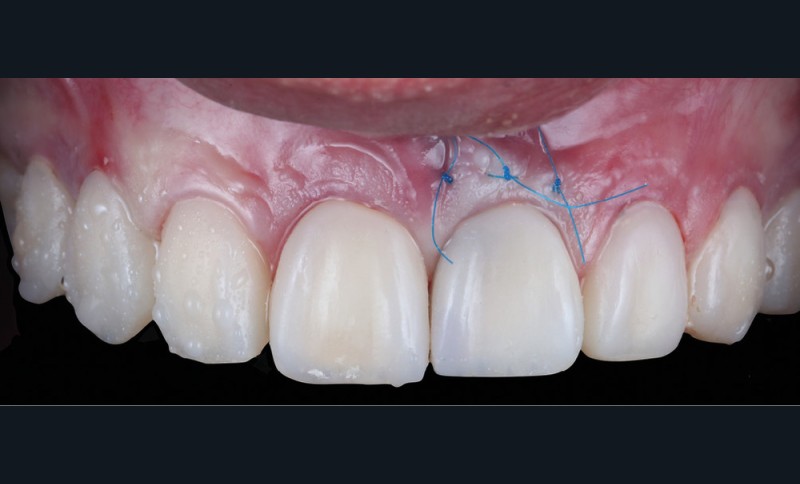

Acte 3 : gestion du rose soustractive (fig. 3 et 4)

Le laboratoire réalise d’abord un montage en cire (wax-up) à partir duquel une gouttière thermoformée sera préparée au cabinet. L’emplacement des futures dents, et surtout des futurs collets, est objectivé et nous guidera pour notre élongation coronaire. Cette chirurgie correctrice soustractive débute par une gingivectomie. Les collets une fois alignés, nous réalisons une ostéotomie/ostéoplastie. L’os vestibulaire est resséqué et positionné à 3 mm des futurs collets.